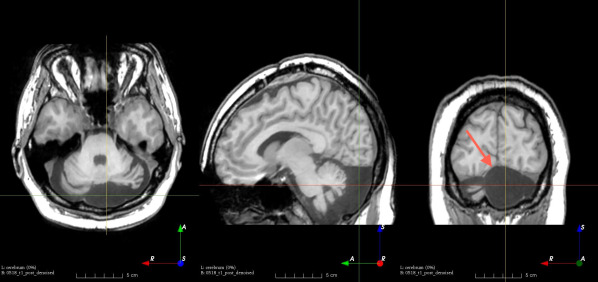

Figure 3: Manual labels from Rater A (green) and Rater D, the model trained with PubFull + EpiPre + Pseudo (magenta). Errors caused by a (a) small resection, (b) blood clot in cavity and (c) brain shift; segmentations corresponding to the (d) 50th, (e) 75th and (f) 100th percentiles giving a DSC of 81.7, 86.5 and 93.8, respectively.

We trained a model using PubFull, EpiPre and Pseudo (2371 images), obtaining a DSC of 81.7 (14.2). Adding the pseudo-labels to PubFull and EpiPre did not significantly improve performance (p=0.176𝑝0.176p=0.176), indicating our semi-supervised learning approach provided no advantage. Predictions from this model are shown in Fig. 3.

Predictions errors are mostly due to 1) resection of size comparable to sulci (Fig. 6a), 2) unanticipated intensities, such as those caused by the presence of blood clots in the cavity (Fig. 6b), 3) brain shift (Fig. 6c) and 4) white matter hypointensities (Fig. 6e). Further work will involve using different internal and external cavity textures, carefully sampling the resection volume, simulating brain shift using biomechanical models, and quantifying epistemic and aleatoric segmentation uncertainty to better assess model performance [24].